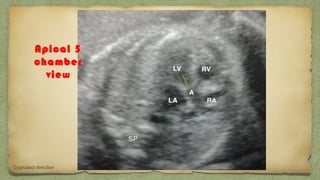

Apical 5

chamber

view

Cephalad direction

๏ฑ 2 ventricles/ walls of equal size

๏ฑ 2 atria / walls of equal size

๏ฑ Foramen ovale moving in left atrium

๏ฑ Pulmonary veins entering left atrium

๏ฑ Motion of mitral valves (left side) regular

๏ฑ Motion of tricuspid valves (right side) regular

๏ฑ Continuity of interventri septum